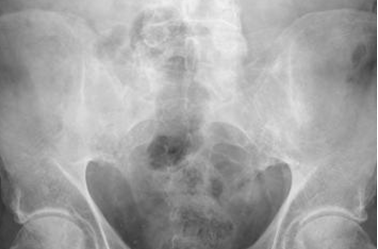

Fig 9. Espondilitis Anquilosante.

Rx AP. Fusión de ambas SI, por espondilitis anquilosante.